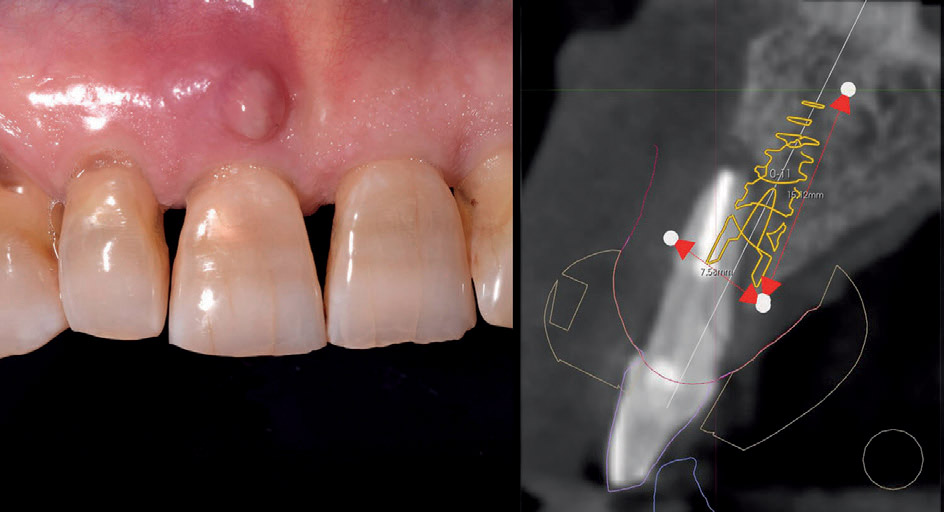

In questo articolo analizziamo il caso di un dente incisivo centrale fratturato con fistola vestibolare (fig.1). Si programma estrazione con contestuale carico immediato.

Fig. 1

Fig. 1